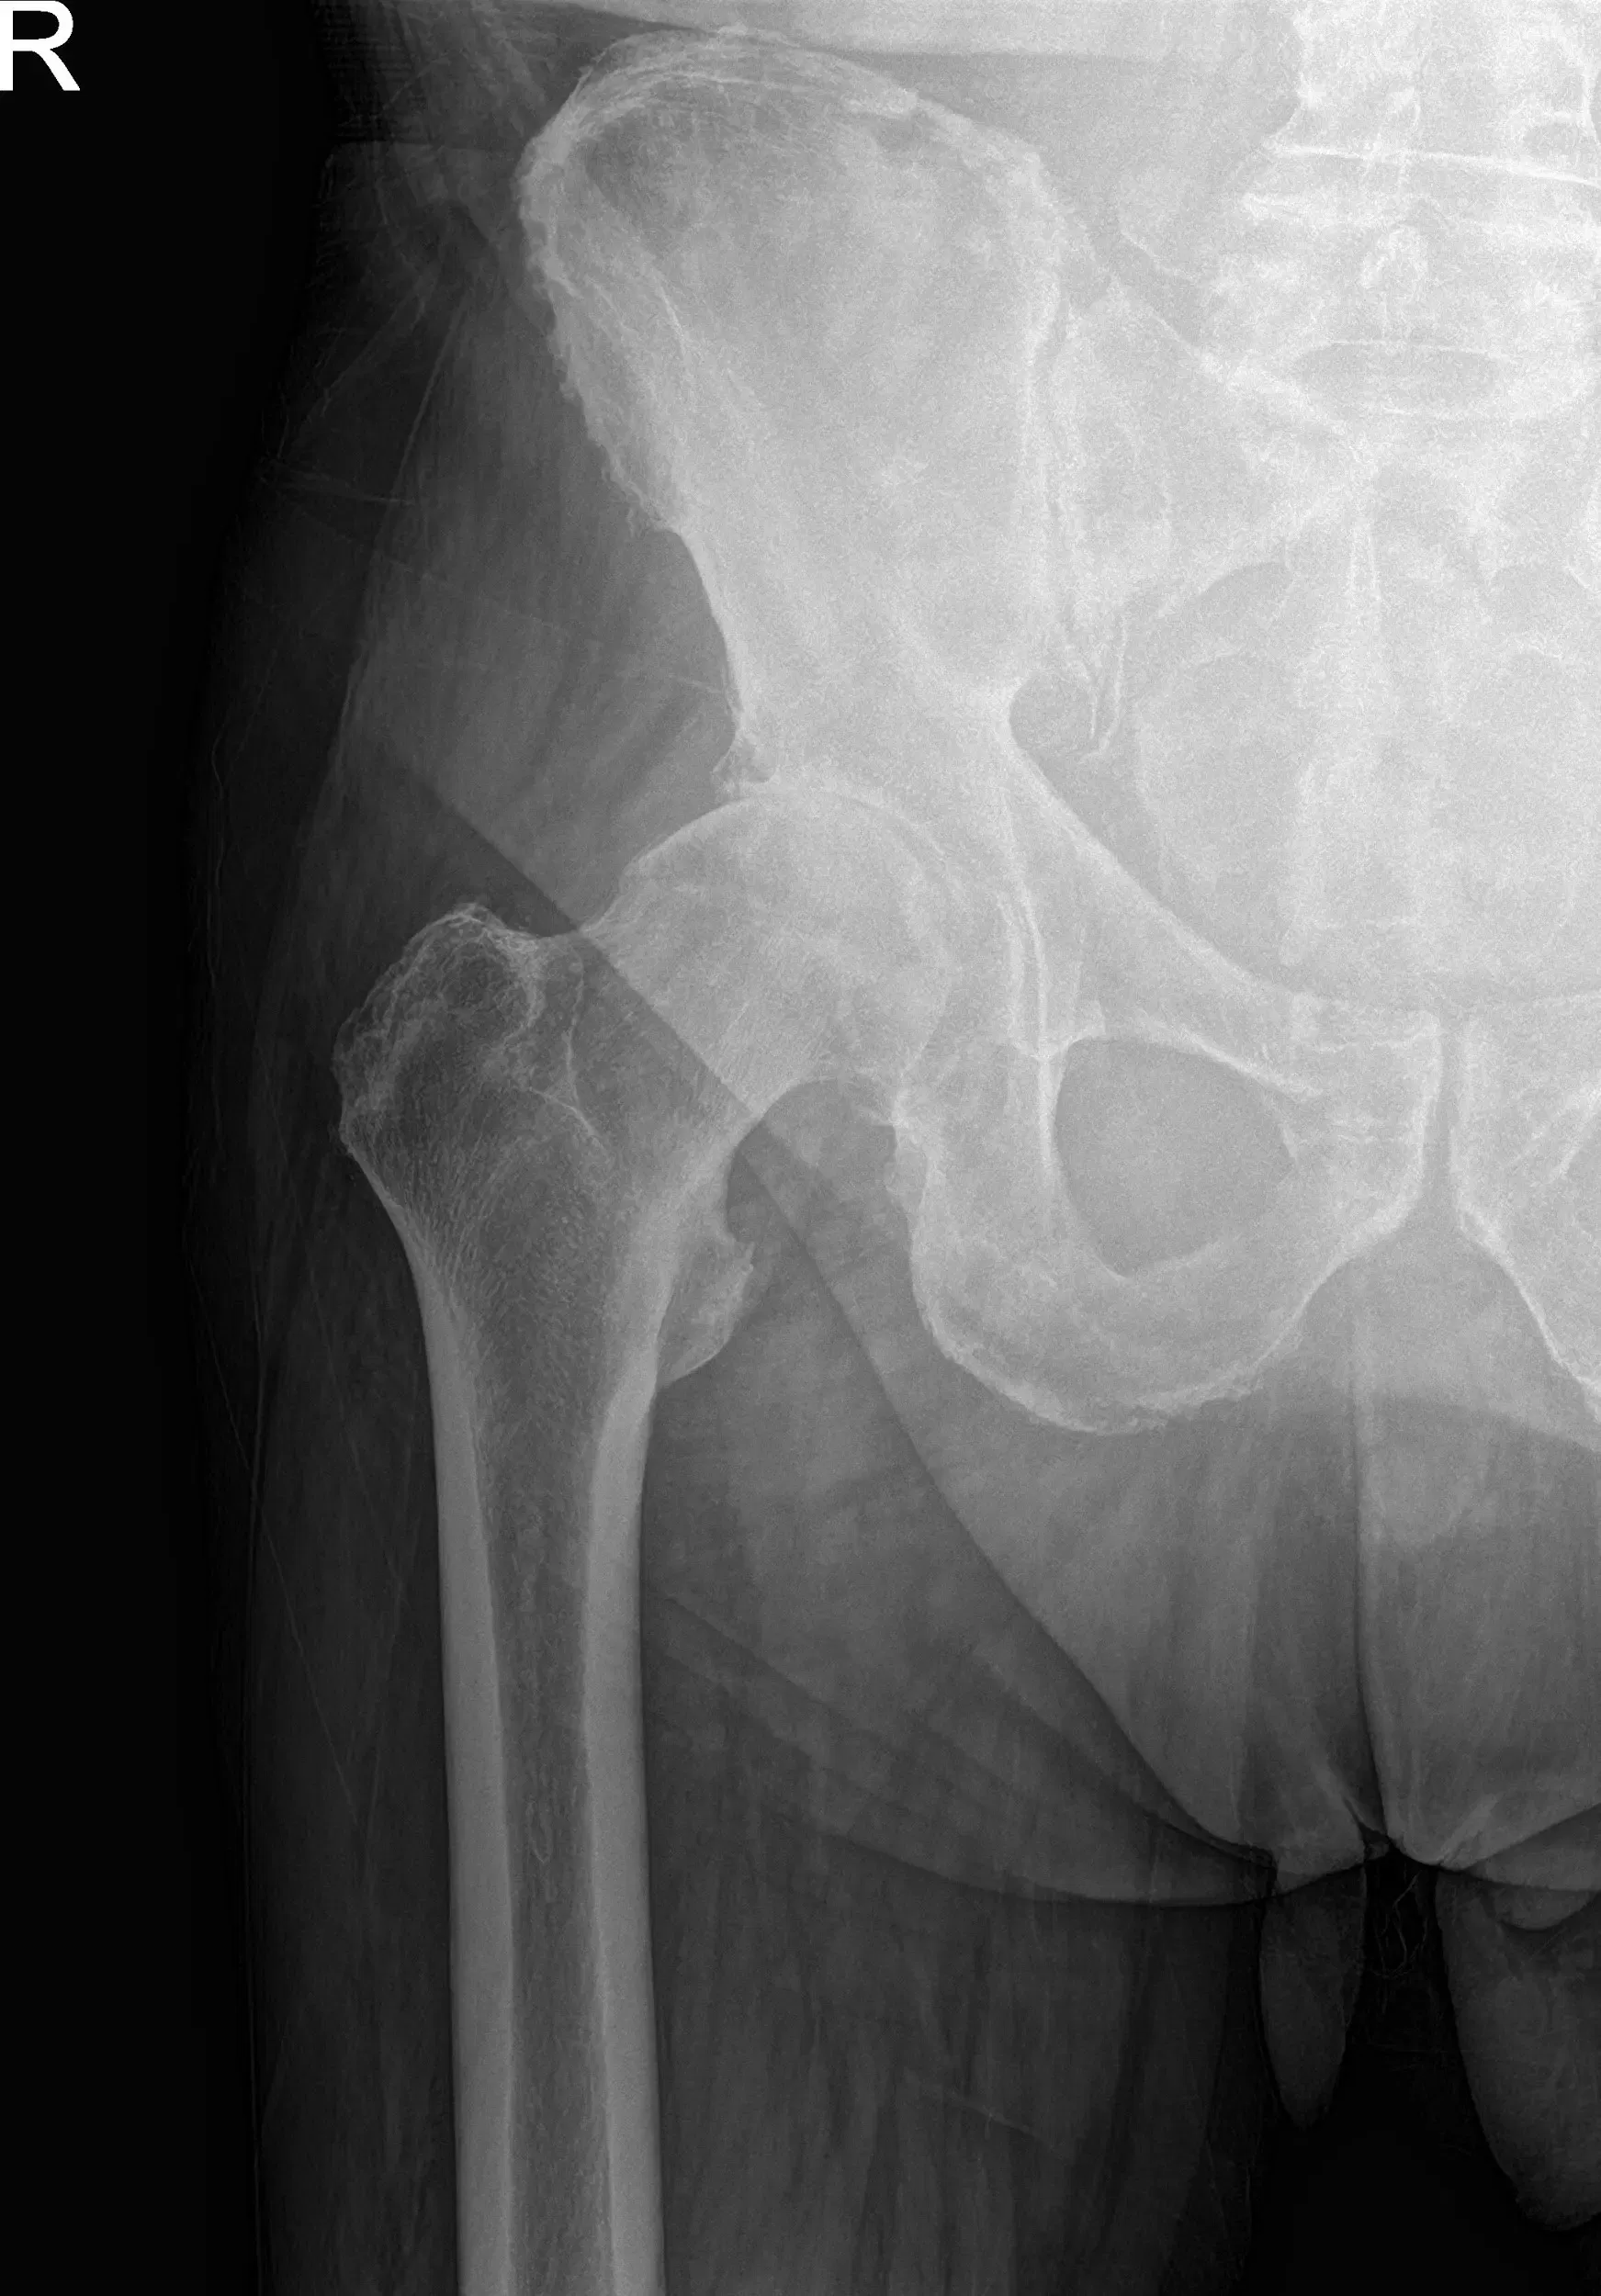

Las radiografías de la pelvis revelaron cambios osteoartríticos en la cadera derecha. Teniendo en cuenta sus comorbilidades y el dolor de cadera que limitaba el estilo de vida, le recomendaron una cirugía de reemplazo total de cadera. Se le informó del riesgo añadido de la cirugía debido a la fibrilación auricular y la hipertensión.